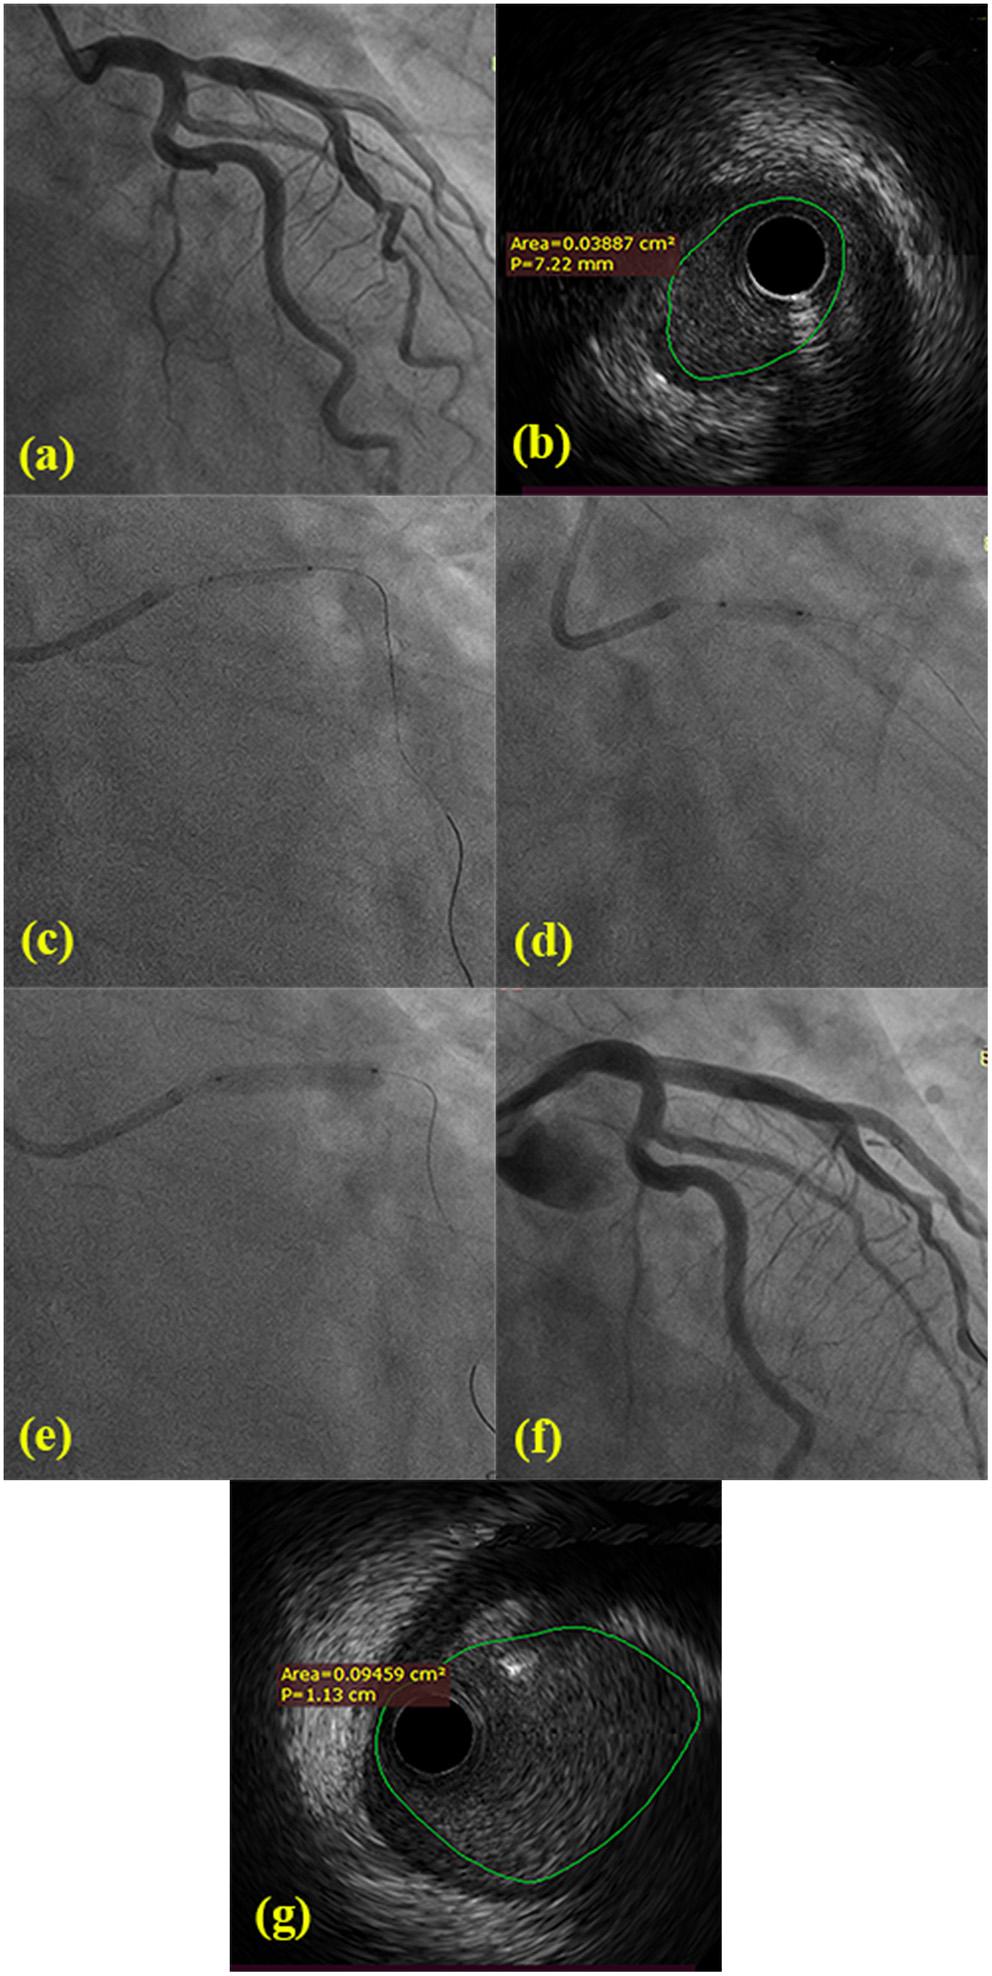

DCB angioplasty (SeQuent Please, B.Braun Interventional Group, Ltd, Melsulgen, Germany) with a bailout stenting strategy was conducted according to international guidelines and the current consensus (14). Target lesions were pretreated using standard balloon angioplasty, a non-compliant balloon, and/or cutting balloons. After achievement of minimal residual stenosis, the DCB (recommended diameter was 0.8–1.0:1 of nominal target vessel size) could be inflated for 30–90 s. In cases of residual stenosis >50% or type C coronary dissections, a stent was implanted only as a bailout for the treatment of suboptimal results after DCB. Intravascular ultrasonography (IVUS) was not routinely performed. IVUS imaging was conducted by a commercial scanner (Boston Scientific Corporation, Marlborough, MA) and performed after intracoronary administration of 0.2 mg nitroglycerin to identify the gradient of calcification, measure external elastic membrane area and the minimum lumen area of major and side branch pre- and post-intervention, and provide a precise diameter reference (as shown in Figure 1).

Figure 1

(a) Angiology showing 80% ostial stenosis of LAD and normal LMB and LCX from two different angles. (b) Pre-procedural IVUS confirmed the minimal lumen area of LAD ostial lesions. (c) The 2.0 mm × 15 mm balloon was pre-dilated at LAD ostial lesions. (d) The 3.0 mm × 10 mm cutting balloon was repeatedly predilated at LAD ostial lesions. (e) The 3.5 mm × 20 mm DCB was dilated with 7 atm × 60 s. (f) The post-procedural angiology showing significant stenosis decreasing. (g) Post-procedural IVUS confirmed the minimal lumen area and the extent of dissection following DCB-only.